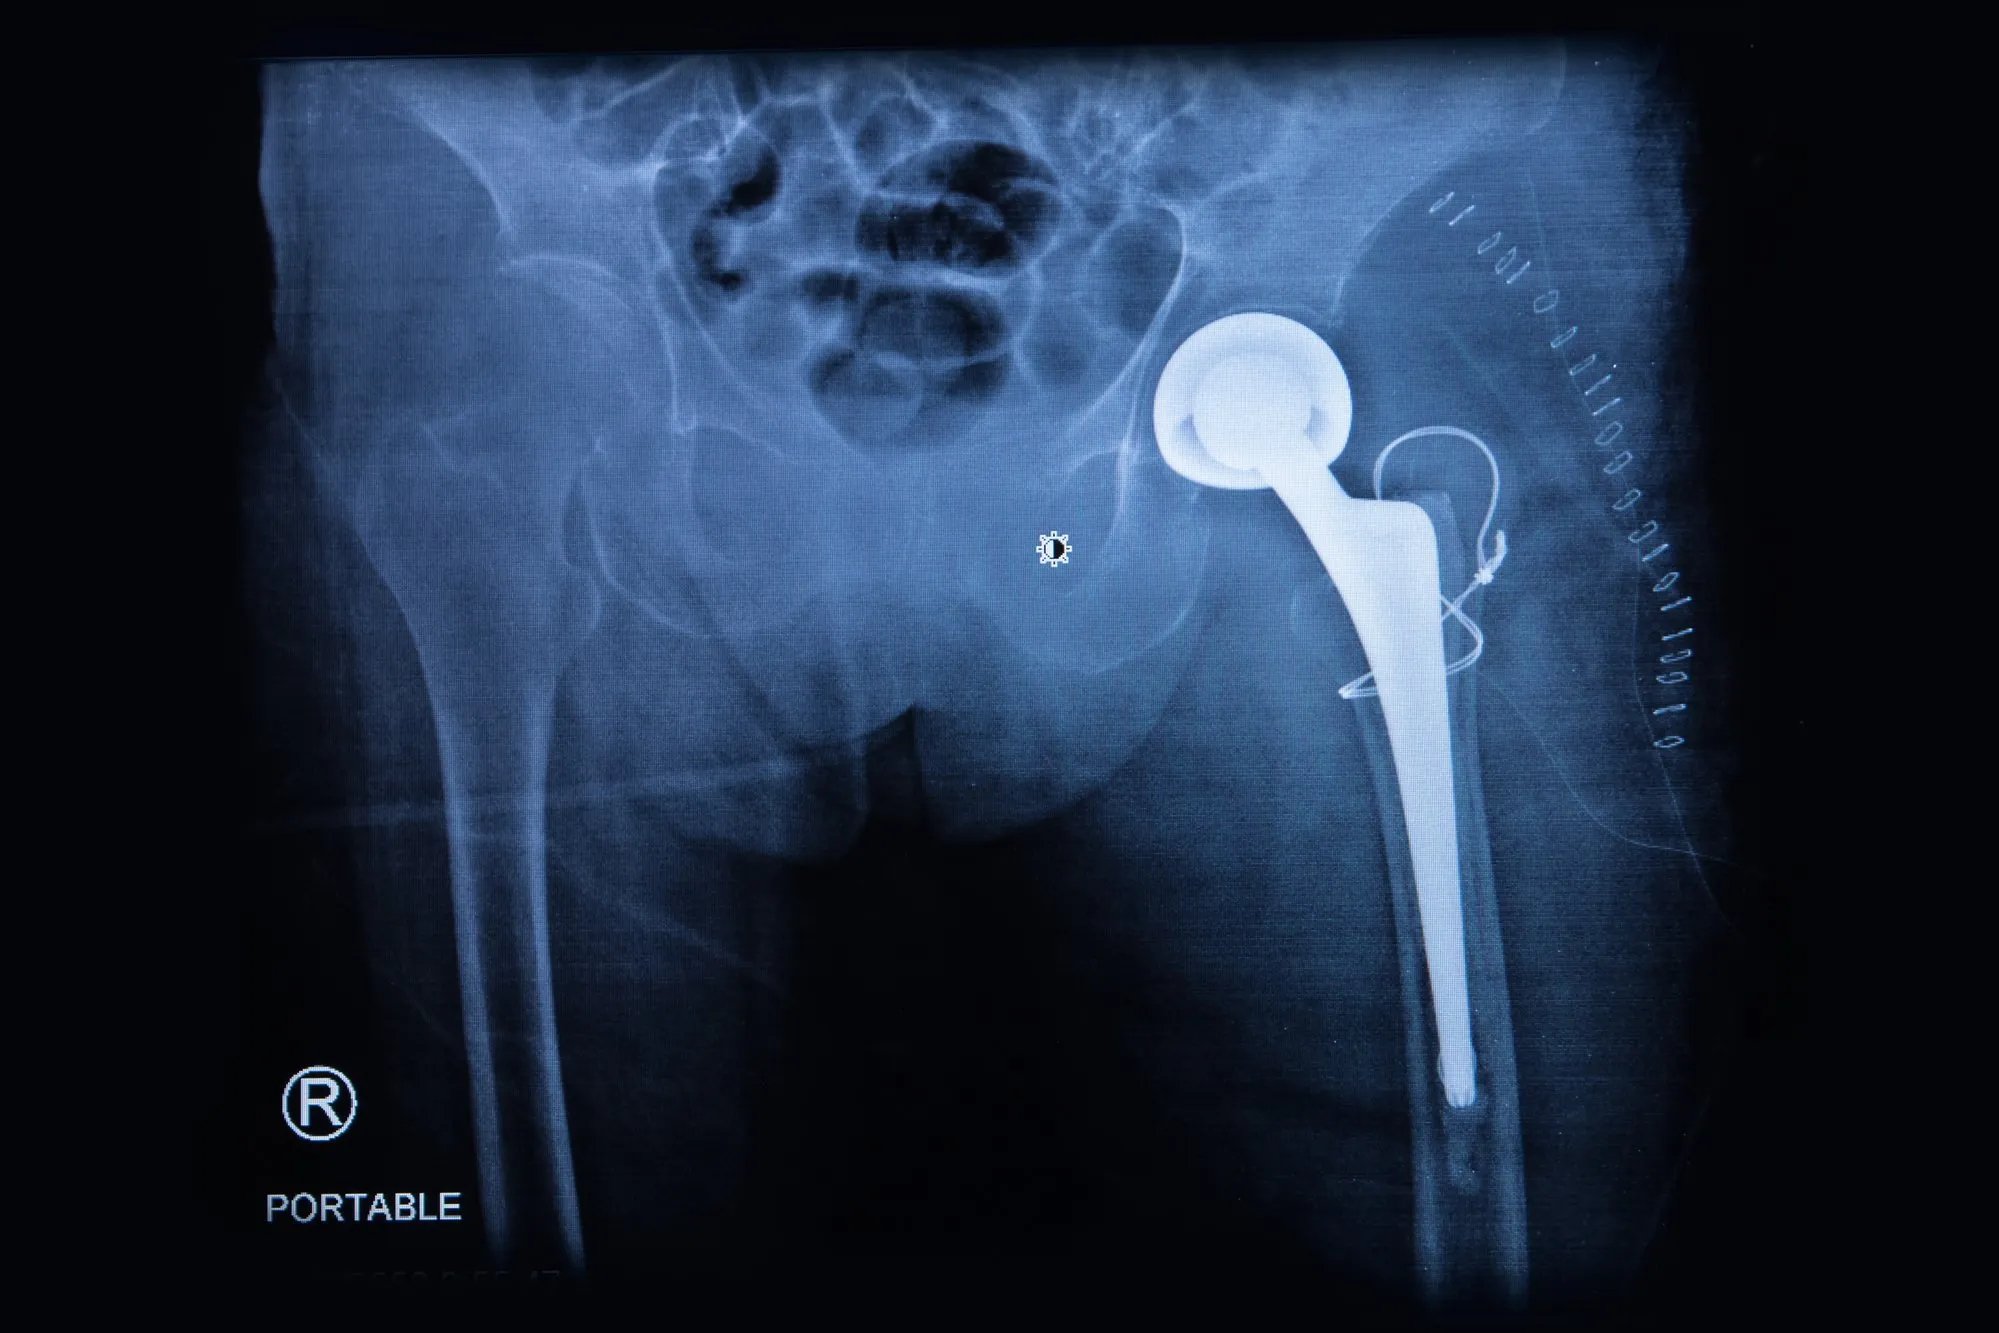

Howmedica Osteonics is the maker of the allegedly defective Stryker hip replacement system, which isn’t “technically” a metal on metal hip implant, but it does have metal on metal components. Holly was the recipient of a Stryker implant, and thought she was getting a safe and effective device.

“In February of 2009, Defendants released the Rejuvenate Modular Primary Hip System (‘Rejuvenate’ or the ‘Product’), which was approved through the FDA’s 510(k) process on or about June 3, 2008. The Rejuvenate system is a dual modular hip replacement prosthesis. It is intended for patients requiring primary total hip arthroplasty or replacement due to joint disease of the hip resulting from non-inflammatory degenerative arthritis,”  the lawsuit states.

“On October 24, 2011, Plaintiff Holly Angus underwent left total hip replacement surgery performed by Dr. Thomas Mulvey, at OSF St. Francis Medical Center in Peoria, Illinois. Plaintiff was implanted with a Rejuvenate Modular stem, neck and other Stryker products. Subsequent to implantation of the Rejuvenate hip, Plaintiff Holly Angus began experiencing discomfort, and a diagnostic workup revealed elevated levels of the metal ions cobalt and chromium.”